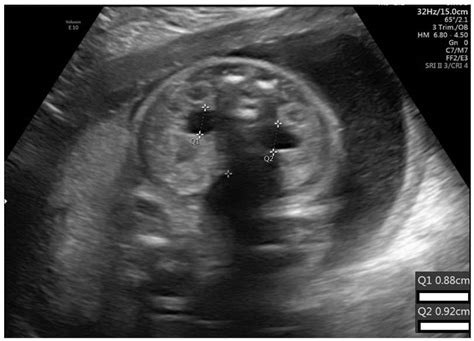

πŸ“ƒ Pyelectasis, unilateral

Learn about pyelectasis of the fetus, a condition involving kidney dilation detected during pregnancy. Discover what this prenatal ultrasound finding means for your baby's health, the importance of follow-up monitoring, and typical outcomes. Gain expert insights into managing fetal renal pelvic dilation to ease concerns and ensure proper care throughout your pregnancy journey.